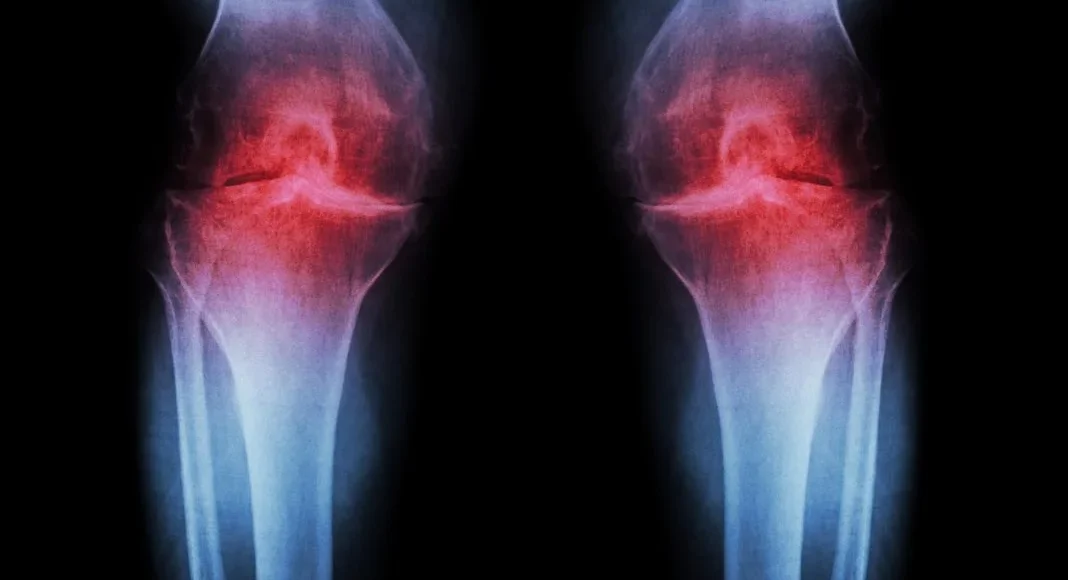

Η ρευματοειδής αρθρίτιδα ξεκινά χρόνια πριν τα πρώτα συμπτώματα

Μια μεγάλη μελέτη διάρκειας επτά ετών αποκαλύπτει ότι η ρευματοειδής αρθρίτιδα (ΡΑ) δεν εμφανίζεται ξαφνικά τη στιγμή που αρχίζουν οι πόνοι στις αρθρώσεις.

Αντίθετα, φαίνεται πως η ασθένεια ξεκινά πολύ νωρίτερα, με αλλαγές στο ανοσοποιητικό σύστημα που εξελίσσονται «σιωπηλά» για χρόνια.